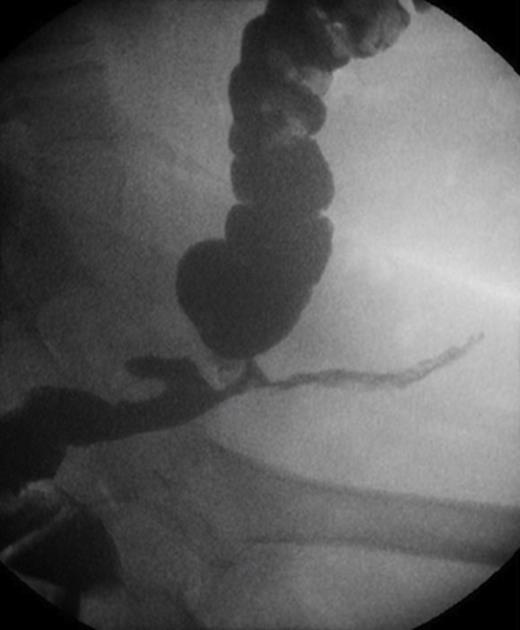

At a clinic review two months post Hartmann’s reversal, the patient complained of intermittent discharge from the lower end of her laparotomy wound associated with per-rectal intermittent discharge of mucous and blood. Contrast Studies had revealed the presence of an anastomotic stricture complicated with a colo-cutaneous fistula (Figure 1).